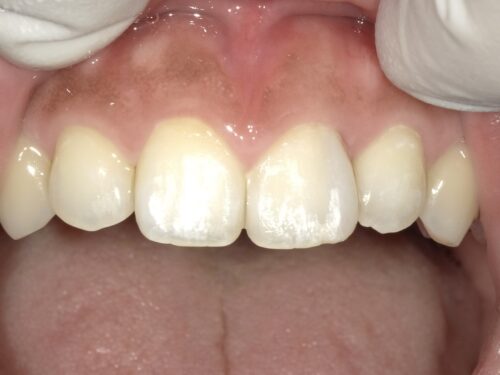

こちらがホワイトニング後の写真です。

A1という色と同じくらい歯が白くなりました。

するとどうでしょう。

古くなった詰め物の色が最初よりも、より際立ってしまっているのがわかります。